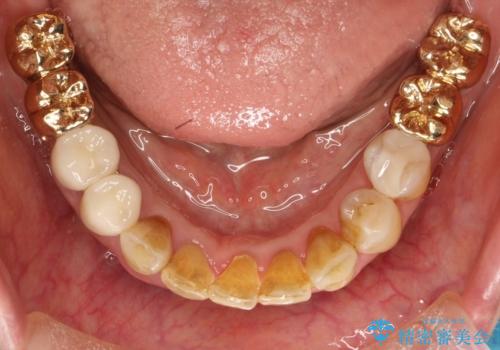

片顎の部分矯正 ワイヤーを用いて短期間でガタつきを改善する

- 歯列から逸脱した歯を1本抜歯し、ワイヤーを用いて短期間で歯列をきれいに整えた。

下顎の歯列を整えることで、上の歯に対して無理な咬み合わせで強い負担がかかることもなくなり、また歯ブラシもしやすくなることで、長期的に良い環境を整えることにつながります。